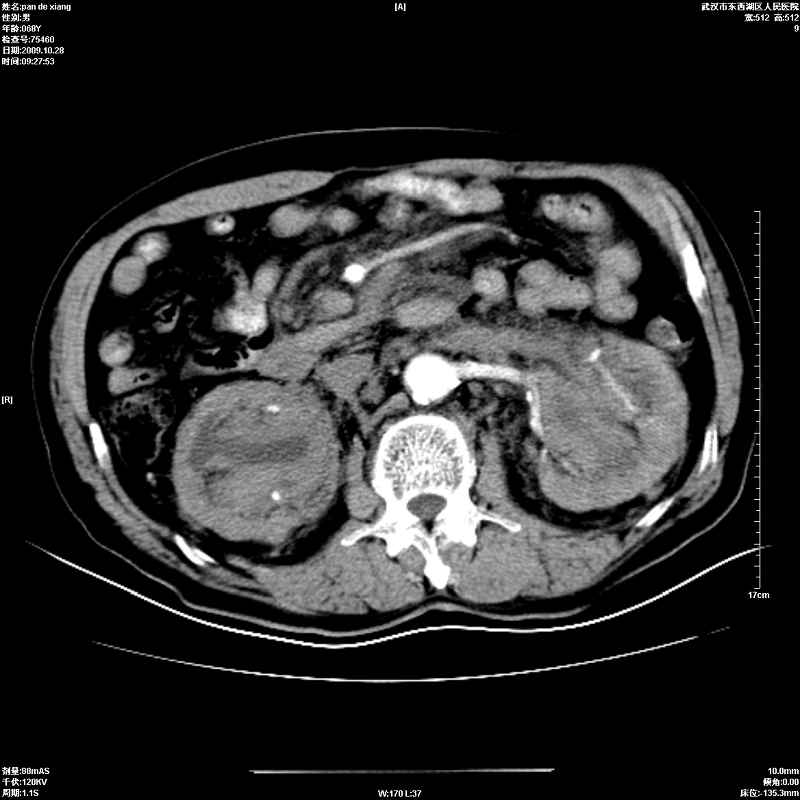

以下是引用杀毒软件在2009-10-28 20:41:00的发言:[br]结合临床考虑---白血病双肾改变或淋巴瘤。

以下是引用zxl51642在2009-10-29 9:59:00的发言:[br]结合临床“单克隆免疫球蛋白血症”,考虑双肾为继发损害并肾功能不全(尿中大量igg及少量iga、igm等大分子免疫球蛋白滤出所致继发损害),椎前软组织肿块为髓外造血。与浆细胞瘤有区别,平扫时有战友说的很清楚。